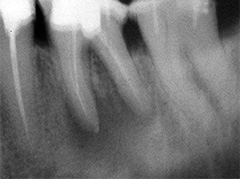

Dieser Zahn wurde schon geraume Zeit zuvor von einer Kollegin im Notdienst eröffnet und anschlies­send mit einer aufwendigen Amal­gamrestauration ästhetisch an­sprechend wieder verschlossen. (Bild 1) Uns blieb noch WK/WF, was bei massiver Überstopfung der hin­teren Wurzel auch gelang (Bild 2).

"Überstopfen ist immer noch besser als Unterstopfen" laut Koçkapan. OK, hier wurde des Guten aber ganz eindeutig zuviel getan.

Also direkt neben dem Zahn das Zahnfleisch ein wenig angehoben und zur Seite gedrängt und dann mit einem scharfen Löffel den Überschuss vollständig entfernt.

Schon 8 Monate später ist eine deutliche Verbesserung der Gesamt­situation unverkennbar (Bild 3). Verlorengegangene Knochensubstanz wurde in Teilen schon wieder aufge­baut, doch ist noch gar nichts entschieden. Schaun mer also ma'.

Abrechnungstechnisch hat der Mut zur WR an 38 gefehlt, deshalb nur EXZ1.